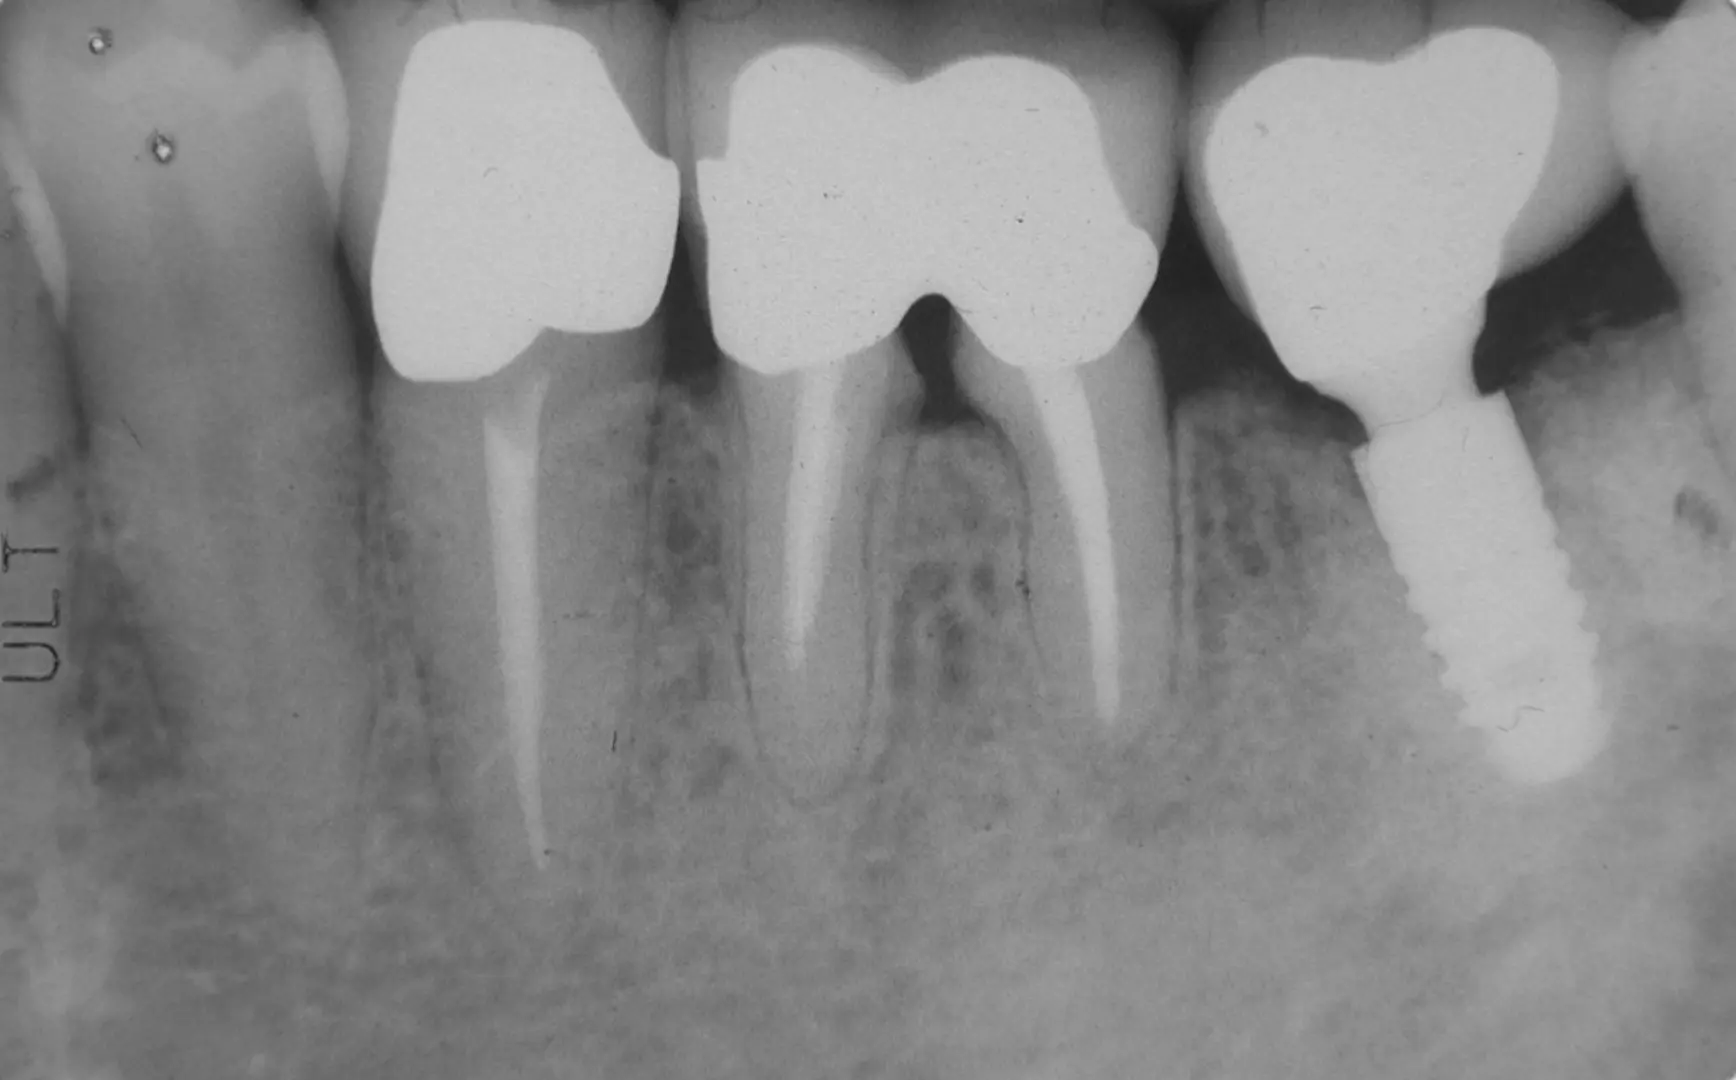

齒槽骨簡單來說,就是負責支撐牙齒的骨骼。打個比方,要長成一棵大樹,下方的土壤至關重要,除了可以供給養分,也能讓樹木因此穩固,而牙周組織對於牙齒的作用也是如此。在牙根下方、包覆牙齒的牙周組織,包含了牙周韌帶與齒槽骨,牙周韌帶的功用在於緩衝牙齒咬合帶來的壓力與供給牙齒養分,而齒槽骨則給予牙齒穩固的力量,透過緊密包覆帶來堅固的牙齒。

造成齒槽骨流失的原因不只一種,撇除特殊先天性患者的骨質不足因素,後天如嚴重的牙周病、長期缺牙與使用不合的活動假牙都可能使齒槽骨出現流失與萎縮,而其中,全台據統計有超過九成民眾有程度度一的牙周病;65歲以上全口無牙比例更高達26%。從以上兩項數據我們就可以得知,齒槽骨有缺失狀況的患者絕非罕見。

那麼齒槽骨流失會有甚麼樣的影響?來德牙醫指出,齒槽骨流失最直接的影響就是牙齒的穩定性,當骨質越來越少,牙齒除了可能露出牙根、形成敏感性牙齒,更會隨著骨質流失出現牙齒鬆動的現象;當骨質已不足以支撐,牙齒甚至有脫落的可能。

另外,齒槽骨的嚴重流失會造成患者外觀上的明顯差異,當骨質減少,嘴部與臉部都可能出現萎縮不對稱的狀況,影響美觀與患者自信心。再者,骨質不足還會影響牙科的治療,當患者想進行植牙或安裝牙橋,因為骨質的不足,這些治療都會有缺乏穩固性的問題;植牙的手術成功率會因此降低,後續的植牙能使用多久,更是被打上一大問號。從長期來看,齒槽骨流失使得口腔健康受到影響,要進行治療也是窒礙難行,無疑是形成了一個惡性循環。